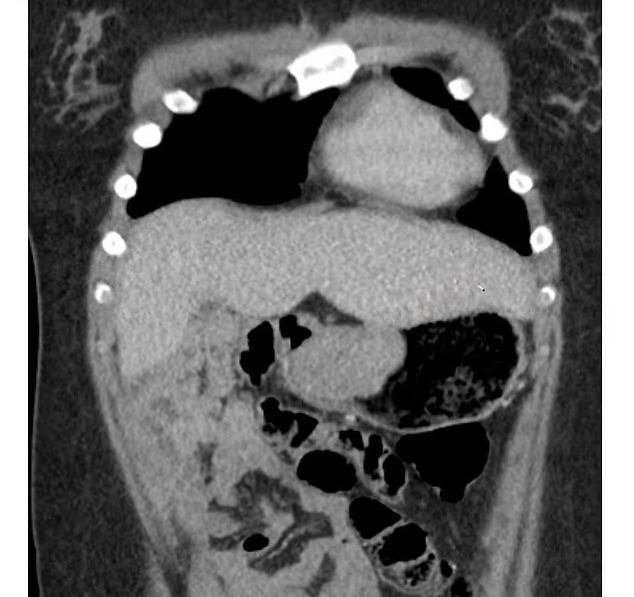

وخلال إجراء منظار للجهاز الهضمي، اكتشف الأطباء أنها مصابة بورم معوي يبلغ حجمه 6 سم داخل معدتها، وهو نوع نادر من السرطان.

أكد الأطباء أن الورم ناتج عن ساركوما، وهو نوع من السرطان يبدأ في العظام أو الأنسجة الرخوة، ويتطور في الجهاز الهضمي ولا يستجيب عادة للعلاج الكيميائي التقليدي.